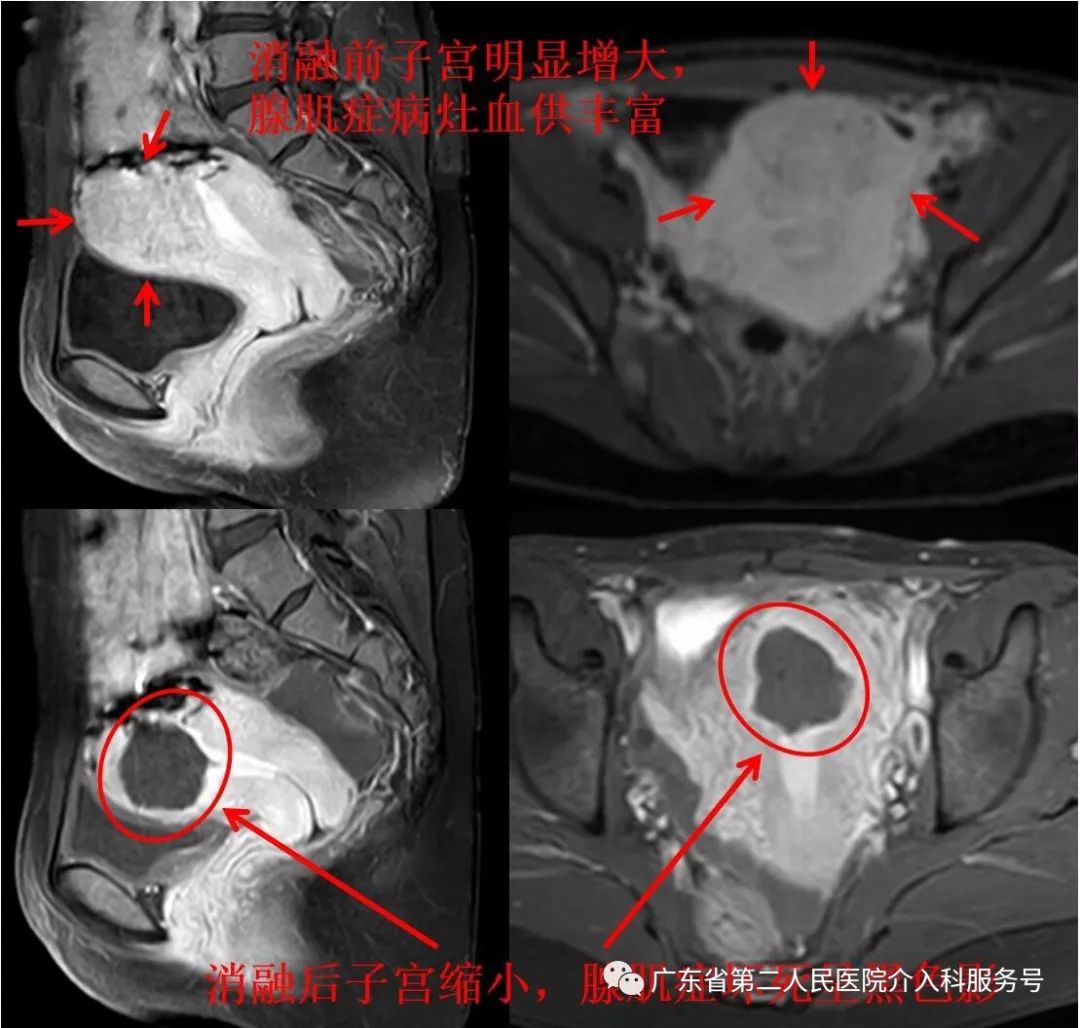

门诊磁共振检查:子宫明显增大(8.2*8.2*11.6cm3),子宫底可见原手术切除疤痕,现子宫腺肌症以前壁明显(如下图)。

介入微创消融治疗后第1天,周女士即可正常下床活动,2天后出院,8天后来例假,无痛经,月经量正常,随后死掉的腺肌症呈褐色分泌物排出;随后三次例假均无痛经,月经量正常,无血块。三个月后复查磁共振示:子宫明显缩小(6.3*5.6*6.8cm3),腺肌症坏死(如下图)。